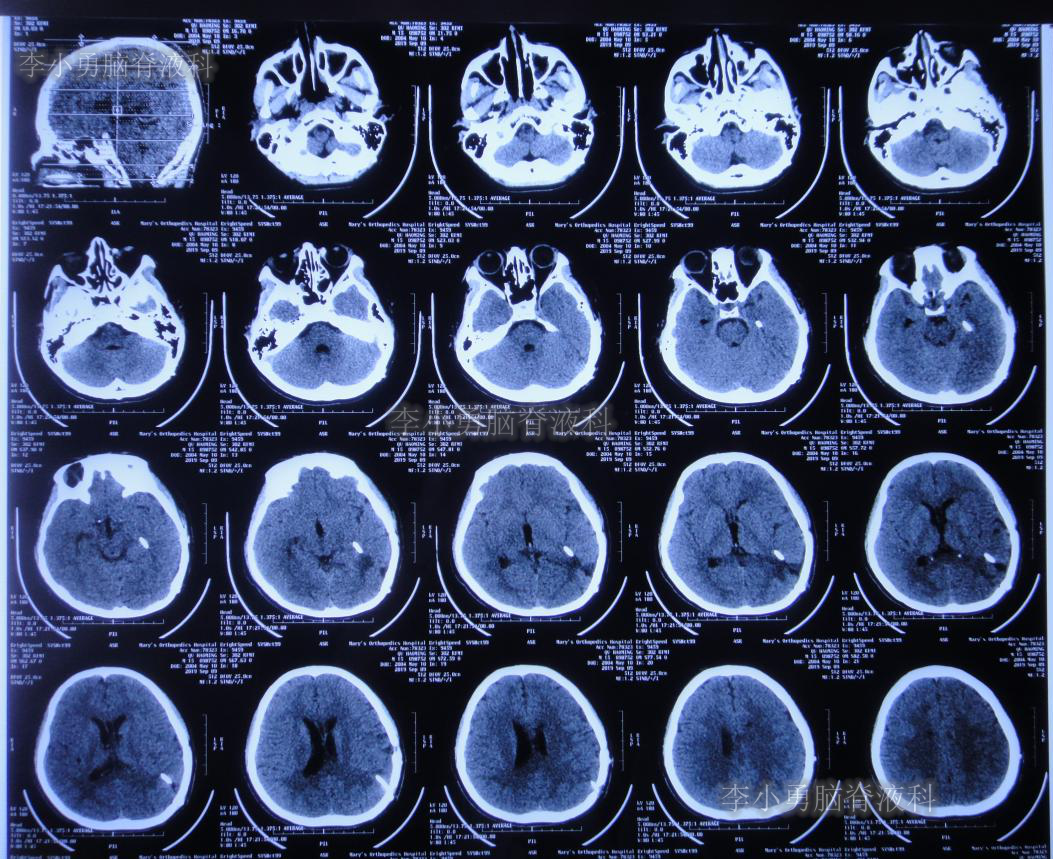

2019年3月26日患者突发头痛及呕吐,随后出现晕厥。急救车送至河南省周口市某医院。行头颅CT(图-1):脑室内出血,次日急诊给予行双侧脑室外引流术(图-2)(第一次的脑室外引流术)。

图-1:2019年3月26日头颅CT:脑室内出血

图-2:2019年3月27日头颅CT:双侧脑室外引流术后